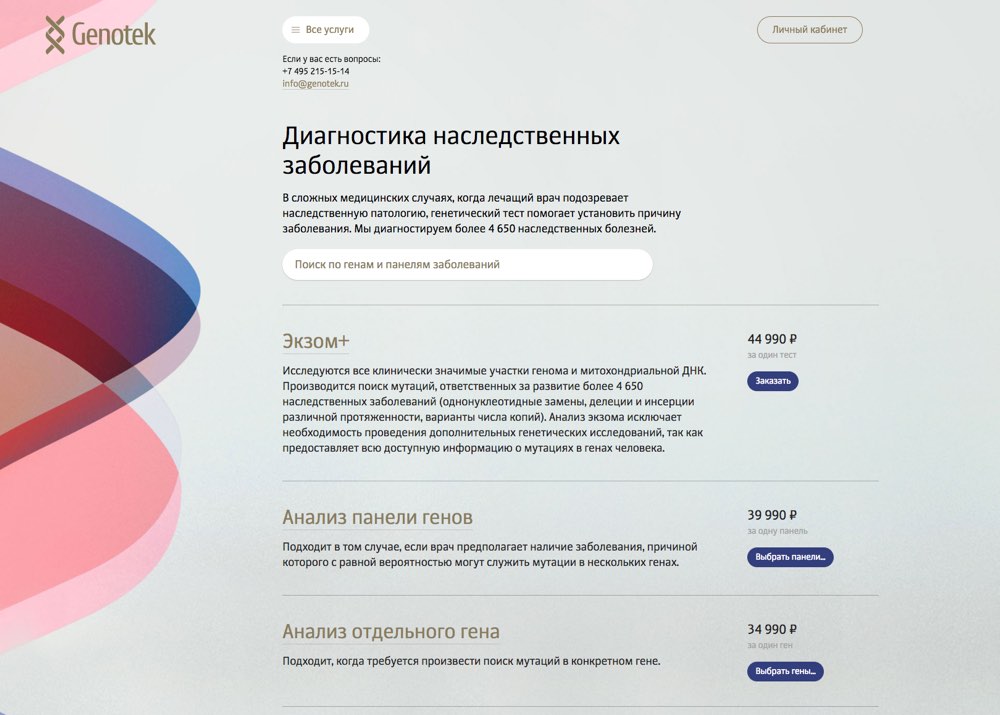

Working on diagnostic tests. Their pages have to contain maximum information since they will be used by doctors and their patients. Not a place for entertainment.

Coming up with the first draft of gene pages.

Getting the client feedback and starting to work on the panels for disorders and mutations. Sketching the appearance of diagnostic test pages.